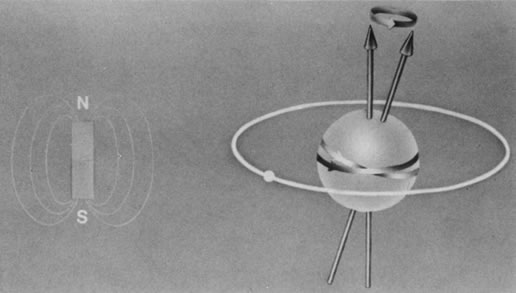

The nucleus of an atom contains protons (positive charge) and neutrons (no charge), and each of these elementary particles spins on its own axis. Because of a relationship between electricity and magnetism, the electric charge and spin of these particles produce a small local nuclear magnetic field. In nuclei with an even mass number (an even number of protons and neutrons), the spinning particles are paired and their magnetic properties cancel. However, in nuclei with an odd mass number, such as hydrogen, sodium, and phosphorus, these spinning particles produce a net magnetic moment. Such nuclei behave as magnetic dipoles and respond to external magnetic fields (Fig. 1).1,5,11–14

Hydrogen, which contains a single proton, has the largest magnetic moment of all stable atomic nuclei and is highly prevalent throughout biologic tissues. For these reasons, hydrogen forms the basis for MRI and exemplifies its principles. In nature, the magnetic moments of the hydrogen nuclei in biologic tissues are randomly oriented and therefore exhibit no net magnetic effect (Fig. 2). When these nuclei are placed in a strong static magnetic field, such as that produced in an MRI unit, they line up parallel or antiparallel to the field. Slightly more align parallel to the main magnetic field, because this is a lower energy state, and produce a net magnetic vector in this direction (Fig. 3).1,5,8